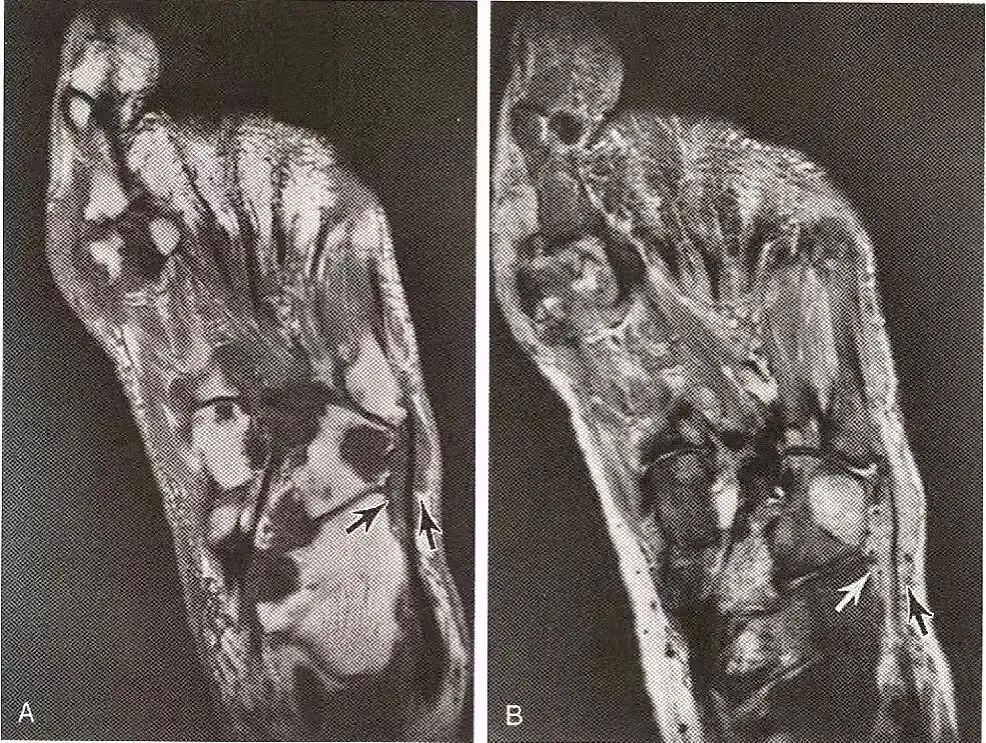

肌腱部分撕裂—纵向分裂:  A,胫后肌(黑色箭号)的大小与相邻的趾长屈肌腱(箭头)相同,表明胫后肌部分撕裂;B,胫后肌腱内裂隙,沿着肌腱的长轴延伸,代表纵向撕裂。